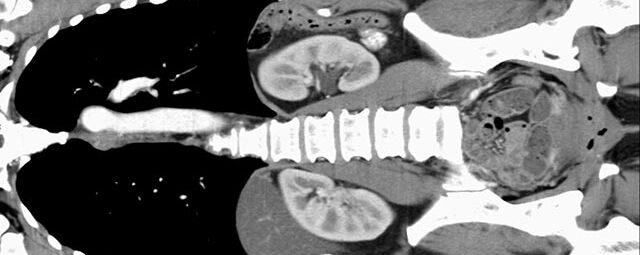

Wirbelsäule

• Darstellung von Frakturen, Tumoren und Bandscheibenveränderungen